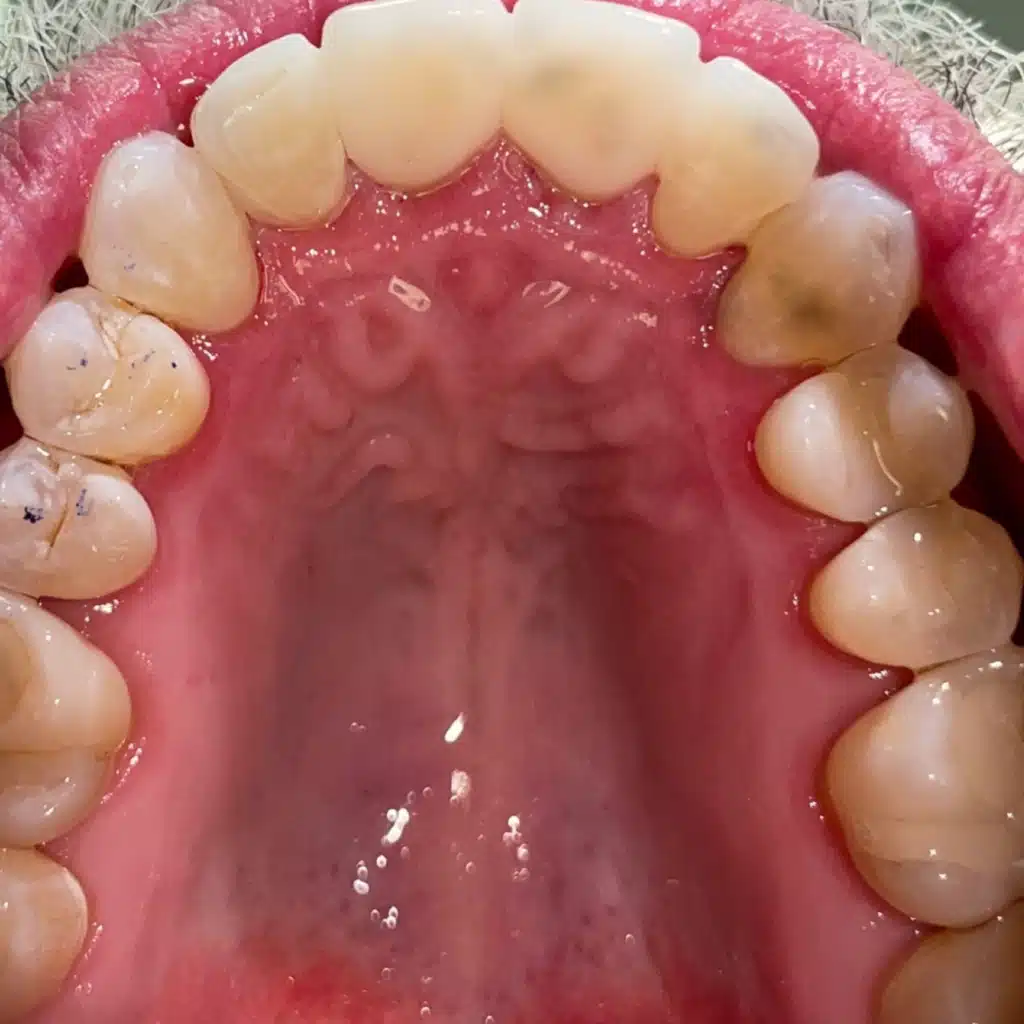

Case study involves Invisalign, Crowns & Bioclear on patient

Smile Reveal #3

Before gettingInvisalign & Crowns

Before

Check out the difference between the two pictures. The patient came to our dental office with issues of teeth misalignment. Our dentist decided to place dental crowns and opt for Bioclear for his set of teeth.